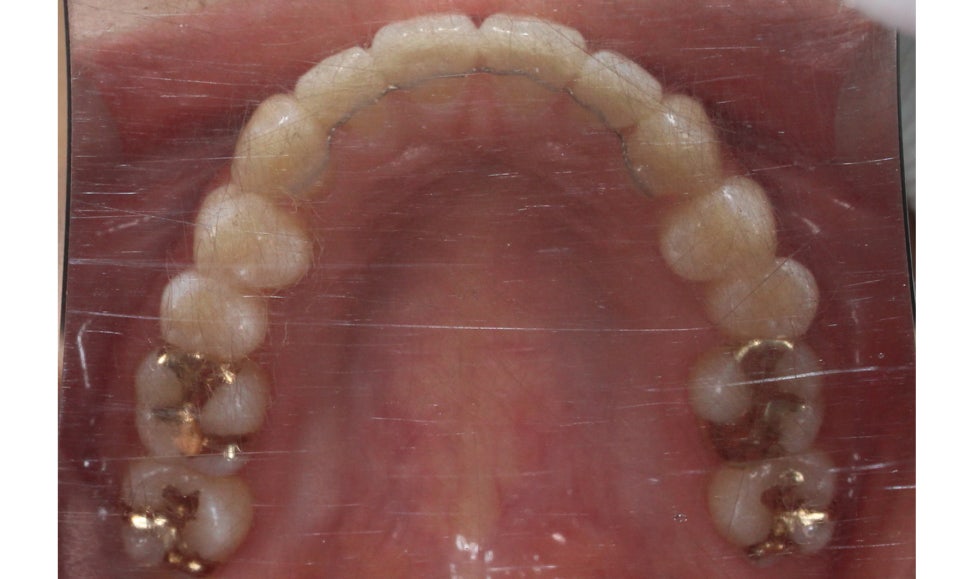

신논현치과 자가결찰브라켓 Case의

교정 전 치아 상태입니다.

상악의 경우 설측으로 뻐드러져 있는

측절치의 바른 교정이 중요한 포인트이기 때문에

이를 중심으로 교정 계획을 수립하였습니다.

또한 미세하게 발견되고 있는 crowding으로 인해

삐뚤어진 정중선 역시 바른 각도로 교정하도록 하였습니다.